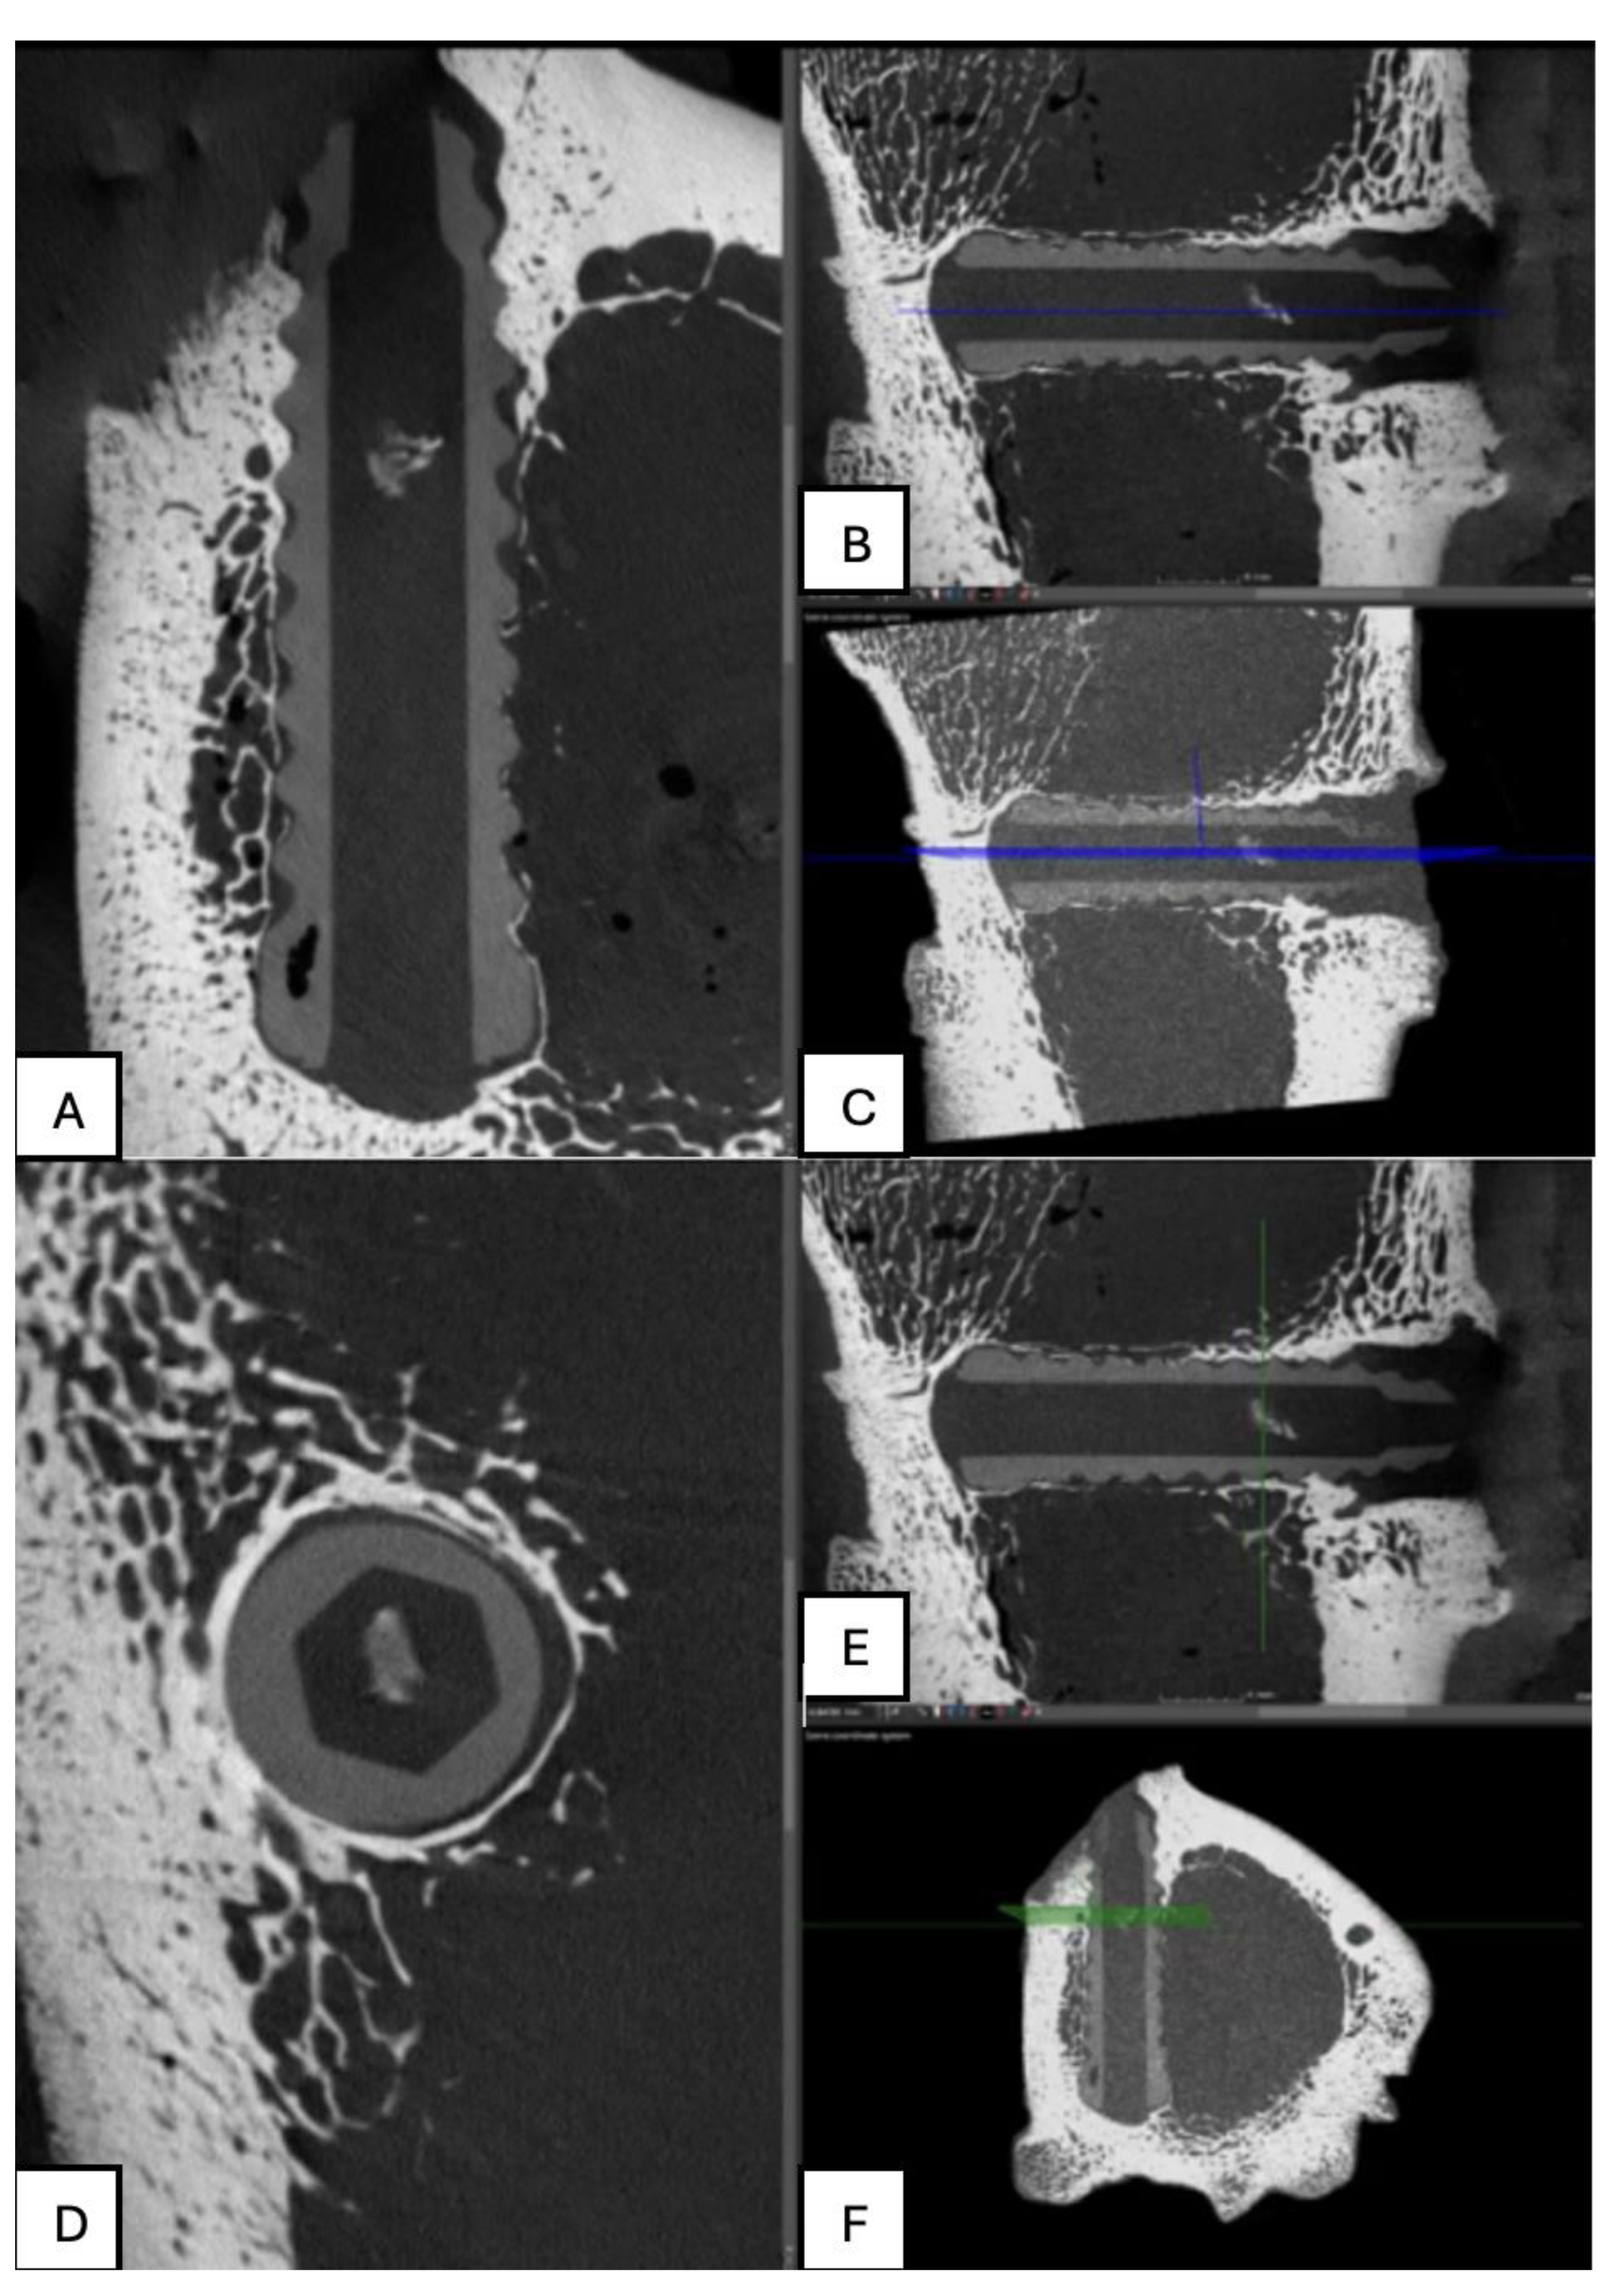

Figure 23. Computed tomography study of the left femur sample, fourth-month post-surgery, with PLDLLA material. (A,B,C,E,F) Sagittal and (D) axial reconstruction.

PLDLLA: In sagittal slices, the screw appears with a circumferential shape, showing slight hyperdensity, which may suggest a bone growth process in that area. Surrounding the crew, a more hypodense area corresponding to the bone marrow is observed. In the lateral projection, the middle third of the screw is seen in contact with the bone marrow, while bone growth is present in the distal and proximal thirds of the implant, contributing to progressive fixation. Additionally, minimal trabecular bone growth is observed around the screw, indicating initial consolidation and integration of the implant into the surrounding bone structure. (Figure 23)

Figure 22. Computed tomography study of the right femur sample, fourth-month post-surgery, with PEEK material. (A,B,C) sagittal reconstruction.

PEEK: In the tomographic study at the fourth postoperative month, the polymer screw (PEEK) is observed following a lateralised trajectory within the medullary canal. In the sagittal and transverse projections, the femoral bone exhibits preserved structural integrity. However, suboptimal trabecular coverage is noted, particularly at the lateral and distal ends of the screw. While the proximal end shows adequate trabecular apposition, the mid to distal regions display insufficient bone integration, especially at the tip of the screw. This suggests a limited osteointegration response in those areas.

The overall bone response indicates mild biocompatibility, with sparse trabecular formation and minimal new bone coverage in the affected zones. Additionally, a few small gas bubbles are visible in the adjacent soft tissues, without signs of significant inflammatory reaction. These findings support a predominantly fibrointegrative rather than osteointegrative pattern at this stage of evaluation. (Figure 22)